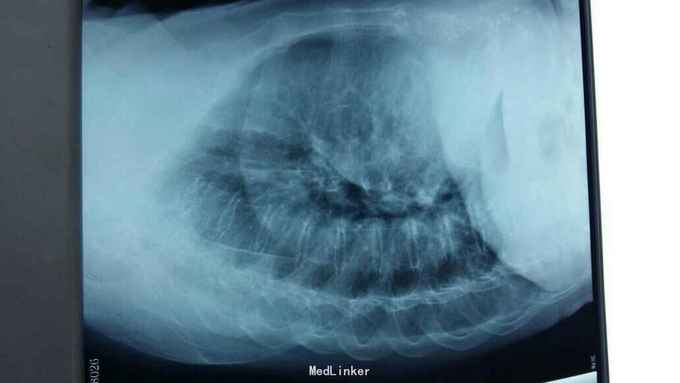

摔伤后胸痛、胸闷1天 1天前在自家劳动时摔伤胸部,伤后胸痛、胸闷,呼吸急促,活动后加重,不敢平卧,为诊治来院。

右侧胸部第4肋及第5胸肋关节处可触及骨摖感,触痛阳性。右肺呼吸音减弱。

1、右侧第4肋骨骨折;2、右侧第5胸肋关节脱位。 1、局部胸带外固定;2、促进骨愈合药物;3、平喘、化痰、预防感染;4、密切观察病情变化,随时复查。

一般外伤导致符合伤多合并血气胸,肺挫裂伤、锁骨骨折,胸骨骨折,胸肋关节脱位,因伤情轻重表现的时间有所不同,有伤后几小时出现有几天不等,病人多伴有呼吸困难,不难判断,胸部CT或三维肋骨成型均可诊断,病情轻观察治疗,较重可手术探查治疗,肺损伤重出现呼吸衰竭行呼吸机辅助治疗,急性期给予正压通气,但不能时间过长,逐步过度。